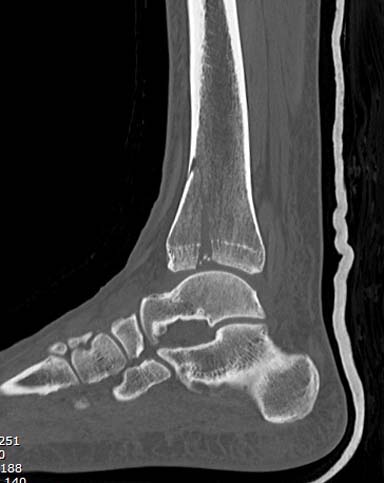

С ответом немного задержался, хотел подобрать материал, но трудно найти идентичный случай. На всякий случай подобрал пару, надеюсь, поможет.

Первый случай, где перелом в результате падения с небольшой высоты, где мортиз рентген снимок показал отстутствие укорочения наружной

лодыжки и КТ срезы подсказали направления атаки. После такой фиксации нет надобности в гипсовой повязке, брейс и через две недели движения в

суставе без нагрузки.